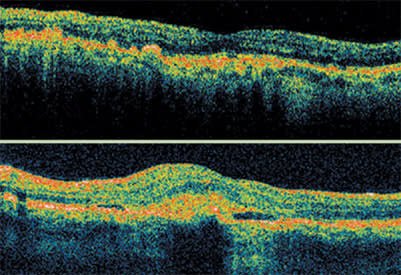

The Stratus OCT continued to detect AMD disease activity after the patient was treated with PDT and bevacizumab. After one injection of ranibizumab, OCT showed a normal retinal appearance and vision improved to 20/30.

This patient received five treatments with pegaptanib sodium (Macugen), but active disease remained. Following treatment with bevacizumab (Avastin), vision and appearance of the retinal anatomy on OCT improved, but some fluid still remained. Treatment with ranibizumab (Lucentis) further improved vision and led to resolution of the retinal fluid. The patient is now being followed with OCT as the sole imaging modality.

As a retinal specialist, I use the Stratus OCT in AMD to determine if fluid is present in the retina. That tells me if the disease is active and requires additional treatment or if I can simply continue to follow a patient. This is especially true in the case of anti-VEGF therapies.